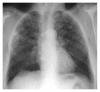

Langerhans cell histiocytosis (LCH) is a rare proliferative disorder of Langerhans cells of unknown etiology. It can involve multiple organ systems with different clinical presentation, which complicates the diagnosis. It can range from isolated to multisystem disease with different prognosis. Although common among children, liver involvement is relatively rare in adults and frequently overlooked. Natural history of liver LCH fits into two stages: an early stage with infiltration by histiocytes and a late stage with sclerosis of the biliary tree. Pulmonary findings are more common and include multiple nodules in different stages of cavitation, predominantly in the upper lobes. We present a case of adult LCH with pulmonary and biopsy proven liver involvement with resolution of the hepatic findings after treatment.